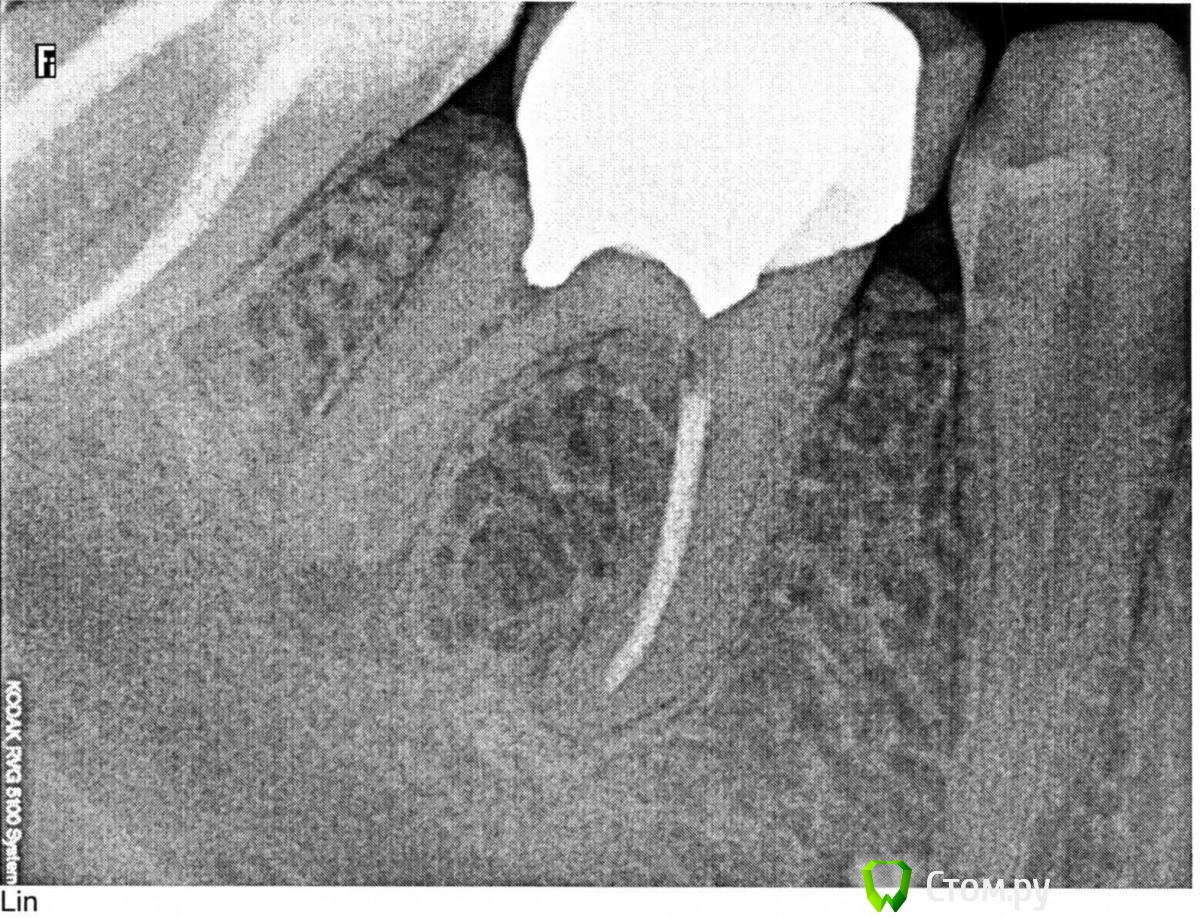

zarubkin Опубликовано 26 ноября, 2014 Поделиться Опубликовано 26 ноября, 2014 (изменено) Предположительно пятый, но можно ли понять точнее по этому снимку и что нужно делать с таким зубом? А может быть шестой? Боль непонятно где точно, как будто откуда-то из глубины идет и между зубами когда чищу ленточкой. Изменено 26 ноября, 2014 пользователем zarubkin Ссылка на комментарий

SDC Опубликовано 26 ноября, 2014 Поделиться Опубликовано 26 ноября, 2014 Предположительно пятый, но можно ли понять точнее по этому снимку и что нужно делать с таким зубом?скорее 6-й. Или заменить зуб на имплантат, Или сделать гемисекцию и удалить только дистальный (задний) корень, сохранив передний. В дальнейшем соединенные коронки на 7-й и 6-й зубы,Или, сняв коронку и убрав вкладку, дать положительную оценку остаточным твердым тканям зуба, провести перелечивание каналов, сделать новую вкладку и коронку на 6й зуб. Ссылка на комментарий